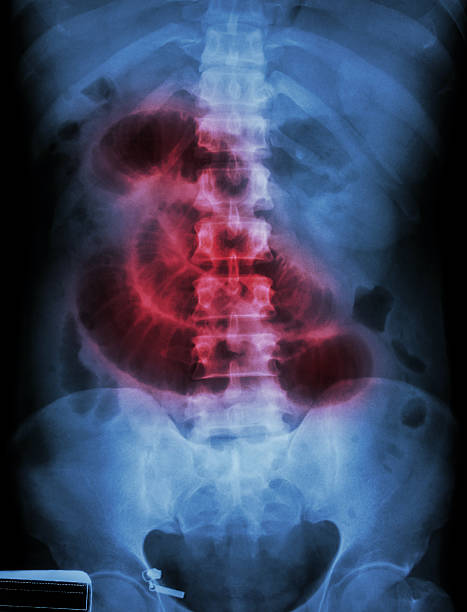

장폐색은 소화관의 혈관이 막히거나 혈액 공급이 감소하여 장 조직의 산소 공급이 충분하지 않아 발생하는 증상으로 여러 가지 불편감을 가지고 오며 빠른 진단과 치료가 이루어지지 않으면 심각한 합병증이 발생할 수 있습니다. 따라서 이번 시간에는 장폐생 원인과 증상 그리고 예방 등에 대해 자세히 알아보겠습니다.

장폐색으로 인한 복통은 일반적으로 속이 아프고 발작적으로 오는 통증이 특징입니다. 통증은 복부 중앙에서 시작하여 전체 복부로 퍼지는 경우가 많습니다. 또한 복통과 함께 소화불량, 구토, 식욕부진 등의 증상도 나타날 수 있습니다.